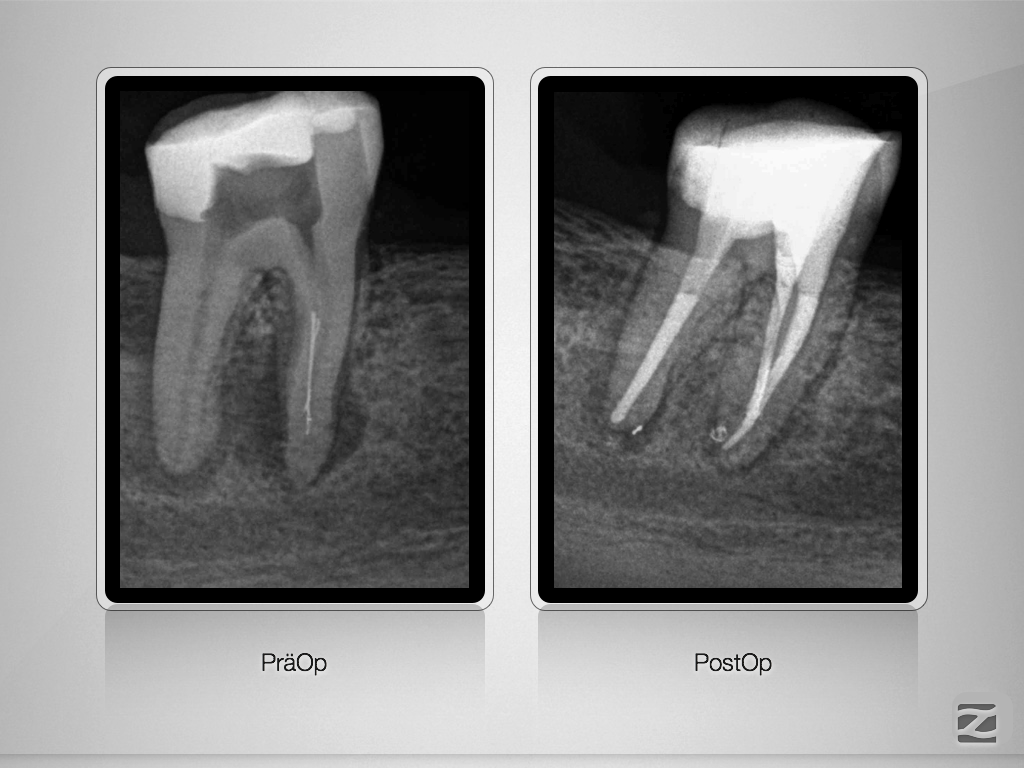

47D.017

8 auf einen Streich